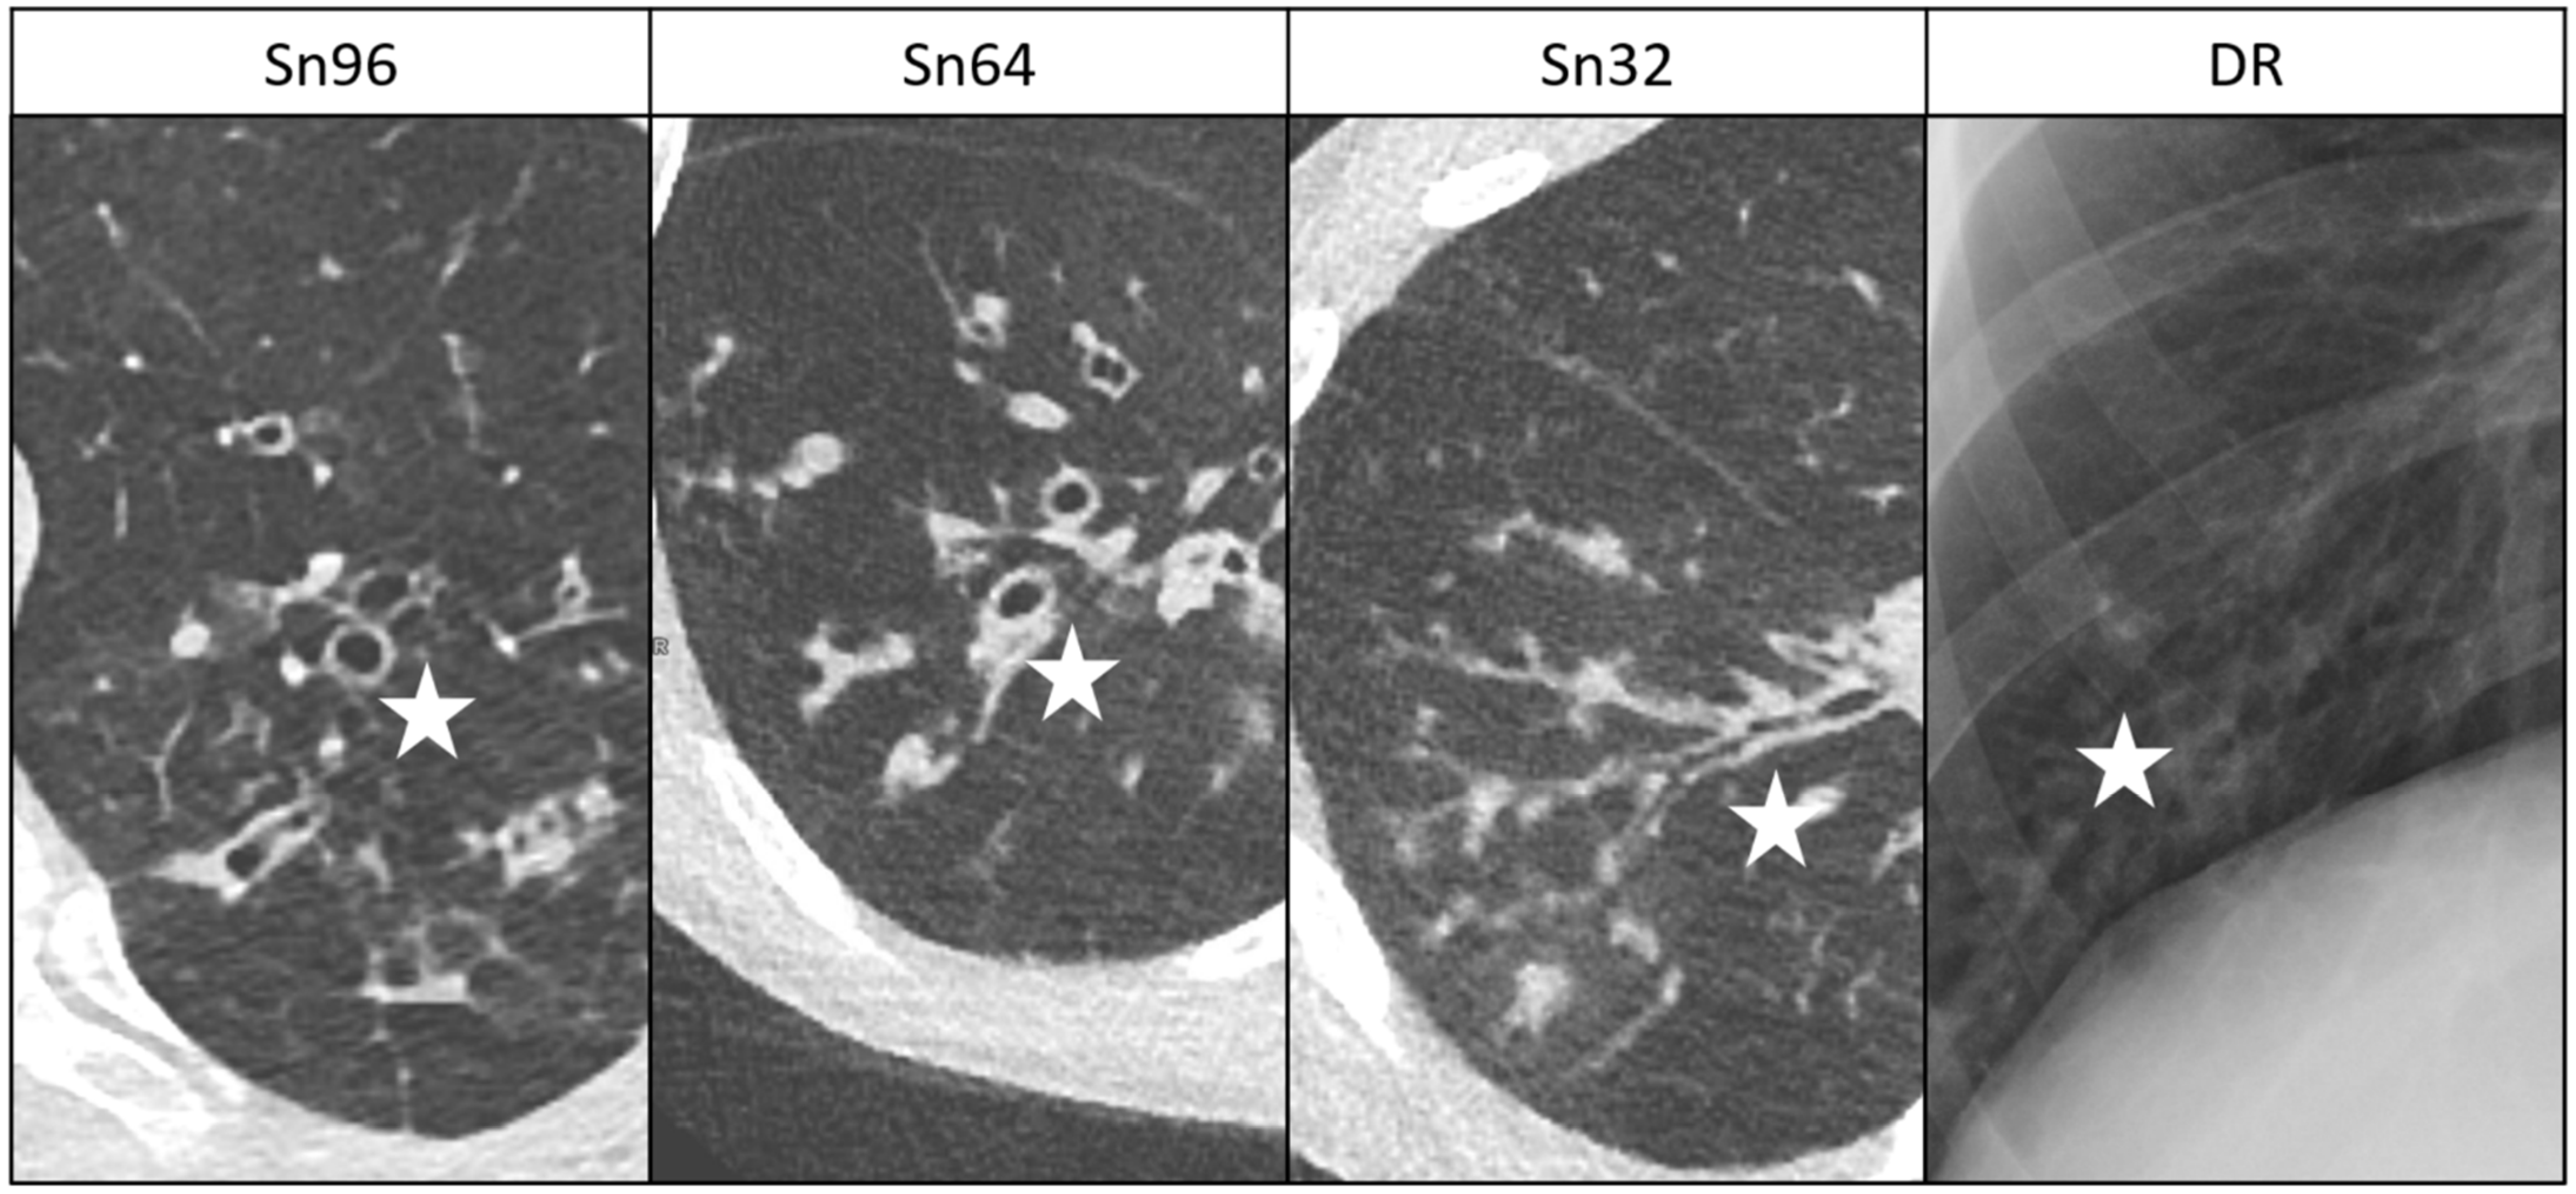

3.3. Suspicious Lung Lesions